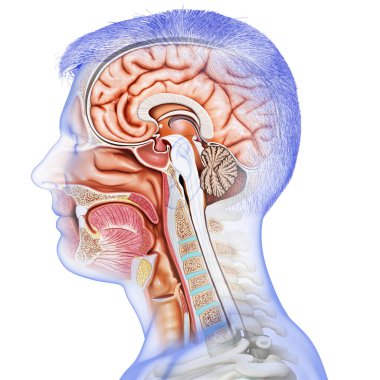

The arterial blood supply to the neck (carotids and vertebral arteries).

İnsanBaşıkanİlaçyüzboğazıBoyunresim çalışmasıprofilNormalbeyinarterkarotidKan damarıKan dolaşımıİnsan AnatomisiSerebral kan dolaşımıvaskülarizasyonsubclavian arteryortak Karotis arterbrachiocephalic Arteryel gövdeVertebral arterfacial arteryserebral artercervical arterytemporal arterydahili şah damarıharici şah damarıdeep cervical arteryBenzer İçerikler